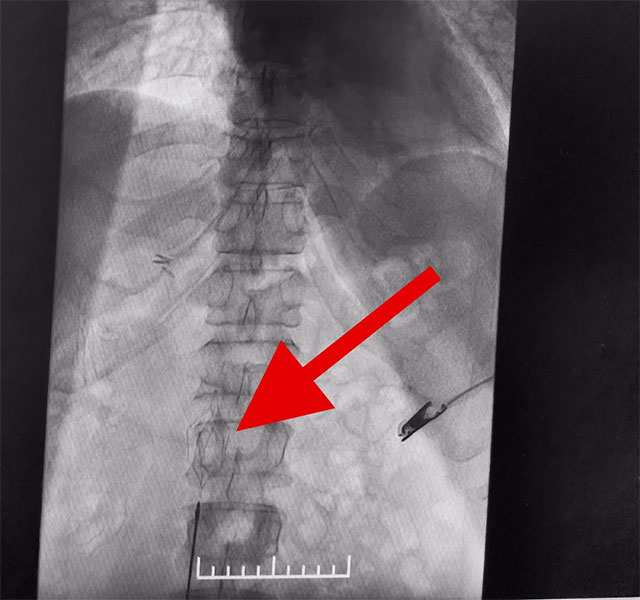

▲ 下腔静脉滤器置入成功

下腔静脉滤器置入是为了预防下腔静脉系统栓子脱落引起肺栓塞而设计的一种装置,分为永久性和可回收两种。可回收滤器可经健侧股静脉、亦可经颈内静脉置入。该手术通过滤器输送器,将滤器在X线透视下送入,确定位置无误后,后撤输送器直至滤器弹开、释放。